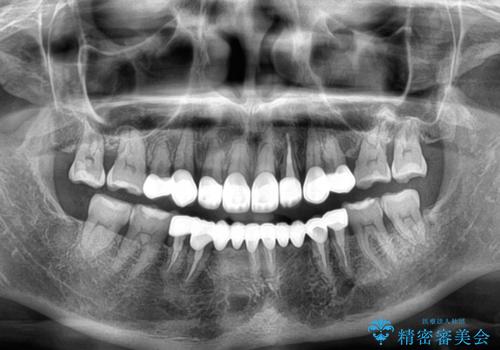

前歯のデコボコおよび奥歯の咬み合わせを改善するために、上顎左右の小臼歯を欠損スペースを利用して歯列を整え、矯正治療後に気になる上下前歯などをオールセラミッククラウンで美しく仕上げていくこととしました。

色や歯列が整ったことはもちろん満足いただけましたが、上顎の舌側転位していた前歯が綺麗に整ったことで違和感が減ったことを非常に喜んでいらっしゃいました。